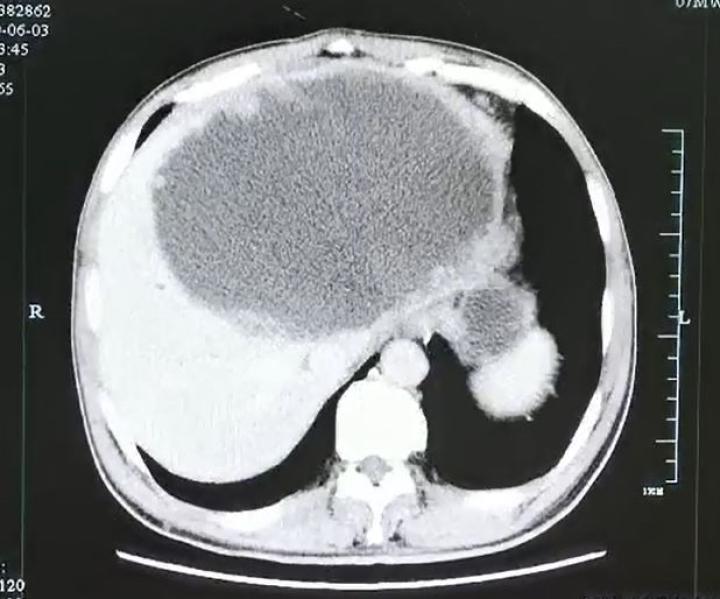

这一检查可把医生和谢师傅都吓坏了,

因为超声影像科检查显示

谢师傅的左肝已经被“掏空”了,

变成了一个大脓球,

医生仔细测量了一下,

大脓球达到19cm×18cm×12cm大小。

入院后腹部CT检查发现肝脓肿壁上长了很多肿瘤样的结构,而且壁很厚。看来这个肝脓肿不简单。